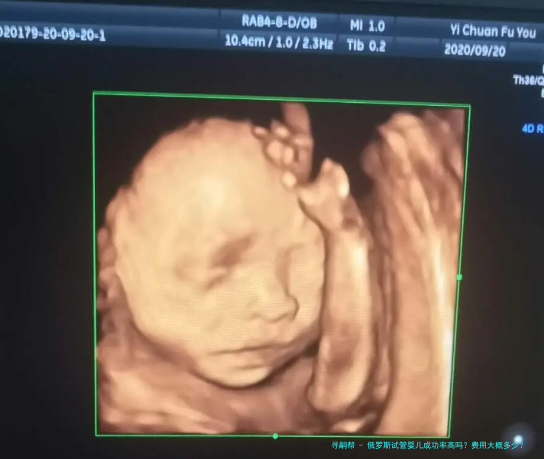

在俄罗斯进行三代试管婴儿的相关攻略和费用关键是此刻很多面临生育困扰的家庭所注意的热点。数据统计显示,俄罗斯的试管婴儿技术在成功率上症状卓越,且相较对于其他,其费用也显得较为亲民。全体而言,进行三代试管婴儿的有关费用大约在2500至5000美元之间。